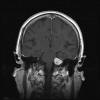

En los últimos tiempos también se ha producido un avance espectacular en lo que a las técnicas de imagen que permiten la visualización del trayecto de los vasos sanguíneos se refiere. Aunque la angiografía convencional (angiografía de sustracción digital) sigue siendo considerada el «gold standard», la aparición de nuevas técnicas cada vez más sensibles y específicas va restando día a día indicaciones a este procedimiento agresivo. En nuestra especialidad, la indicación más habitual para solicitar este grupo de técnicas son la sospecha de parálisis compresiva de III par craneal y la detección de trombosis de seno venoso en el contexto de la hipertensión intracraneal (7) (fig. 4).

Fig. 4: En el estudio de la hipertensión intracraneal benigna, es preciso

solicitar un angioRM en fase venosa (1) para descartar una posible trombosis de

seno venoso. Por la gran variabilidad del patrón venoso muchas veces resulta muy

difícil distinguir entre un seno hipoplásico y un seno trombosado. Asimismo,

determinados hallazgos en la RM o la ecografía, como el aplanamiento de la

esclera posterior (3) o la presencia de una silla turca vacía (2), presentan

combinados, una elevada sensibilidad y especificidad.